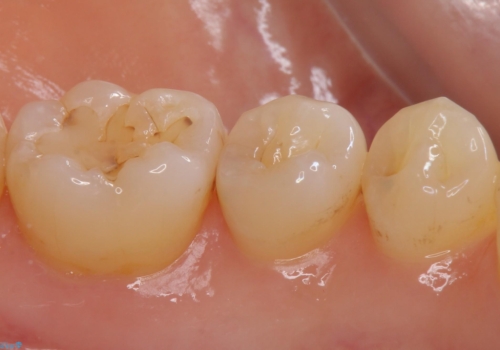

- 奥歯の樹脂の色が気になるとのことで来院されました。

変色しない材料での治療をご希望されたためセラミックインレーでの治療をしていくこととなりました。

- 左下6 セラミックインレー 77,000円×1本費用は治療当時の料金となります

継ぎ接ぎになった樹脂の詰め物から一塊のセラミックインレーに置き換えることで着色や二次う蝕のリスクを抑えます。